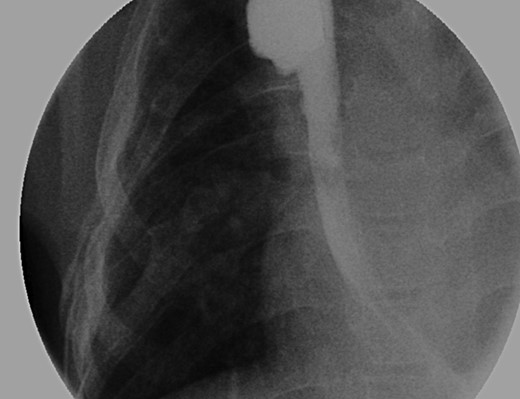

Fluoroscopic examination illustrating incremental ‘growth’ of the distal (lower) esophageal segment while the patient was undergoing external traction (Foker Stage 1). The contrast was injected through her existing gastrostomy tube. The metal dot refers to her esophagostomy; thus, can measure the distance between the ends of her esophageal segments.